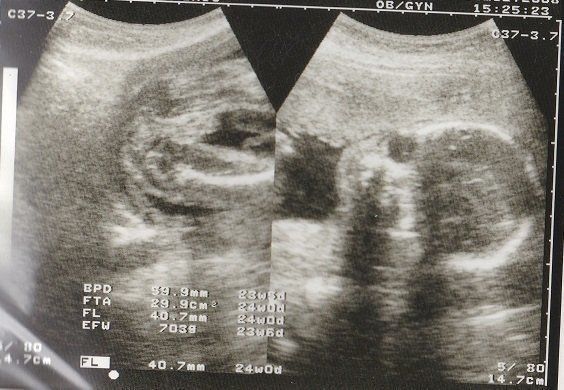

宮本真知さんの妊娠24週目のエコー写真 お顔がなかなか見られない 夏の妊娠はとにかく暑い

夏真っ盛り。妊娠前の半袖ワンピースでどうにか乗り切っていましたが、腹帯なんて暑いものは耐えられず取ってしまいました。妊娠16周目と同じく、BPD、AC、FLを測ってもらいました。赤ちゃんのおおよその体重は606g。3Dエコーでお顔をきちんと見てみようとしますが、やはり手で隠してしまうため、なかなか見られませんでした。これでも顔が写っている一番いい3Dエコー写真です。